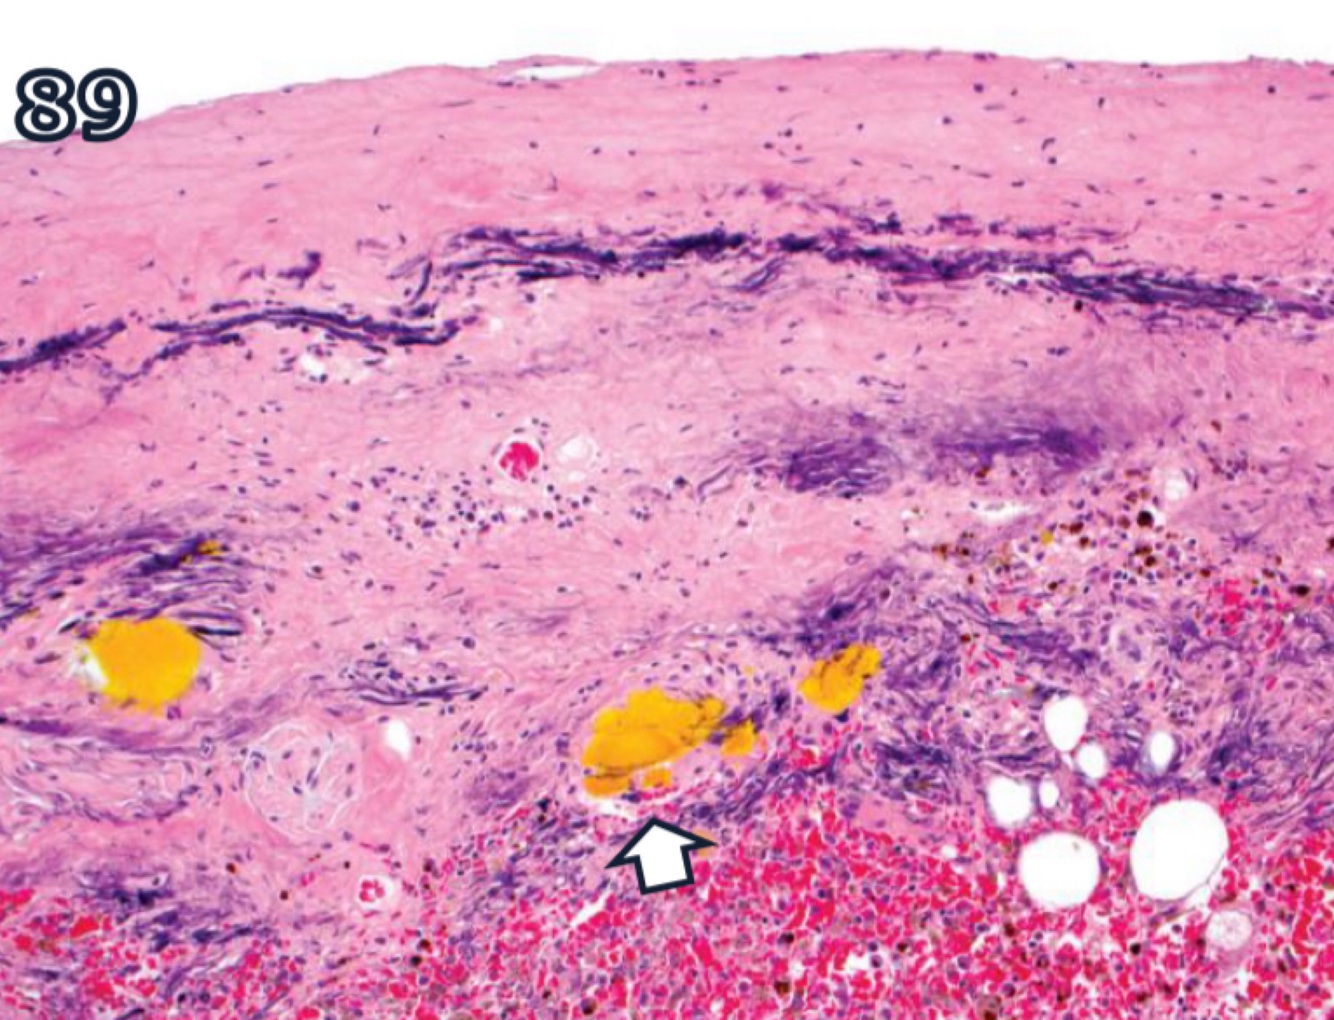

A

free iron is toxic to cells by catalyzing formation of ROS via Fenton reaction

Ferritin present in all tissues, binds free iron + stores it in nontoxic form for use by cell

serum ferritin conc. correlate with iron stores

accumulations of ferritin bound with iron are converted to golden bronw granules of hemosiderin, mainly in macrophages + less so in hepatocytes or renal tubular epithelial cells

prussian blue reaction detects iron of hemosiderin in tissue sections

iron stores most conspicuous in speen + hemosiderosis occurs when there’s increase in erythrocyte destruction

rarely excess iron can be derived from diet or other external sources

presence of hemosiderin-laden macrophages can also indicate chronic passive congestion

if abundant, imparts brownish discoloration to tissues

one of the pigments that typifies a bruise

bright-yellow crystalline pigment derived from hemosiderin but is free of iron

biochemically similar t bilirubin

deposited in tissues at sites of hemorrhage